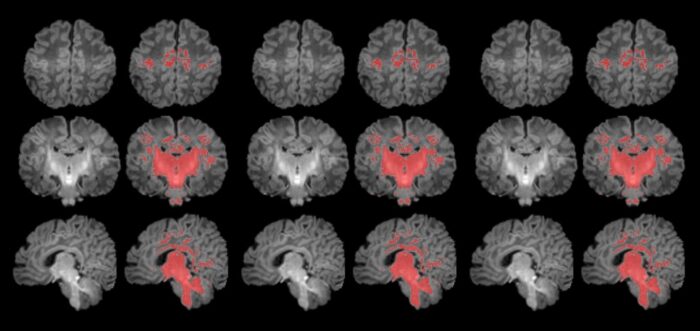

HoliAtlas- Neuroimágenes- Neurodiagnóstico

Uno de los atlas del cerebro más detallado del mundo.